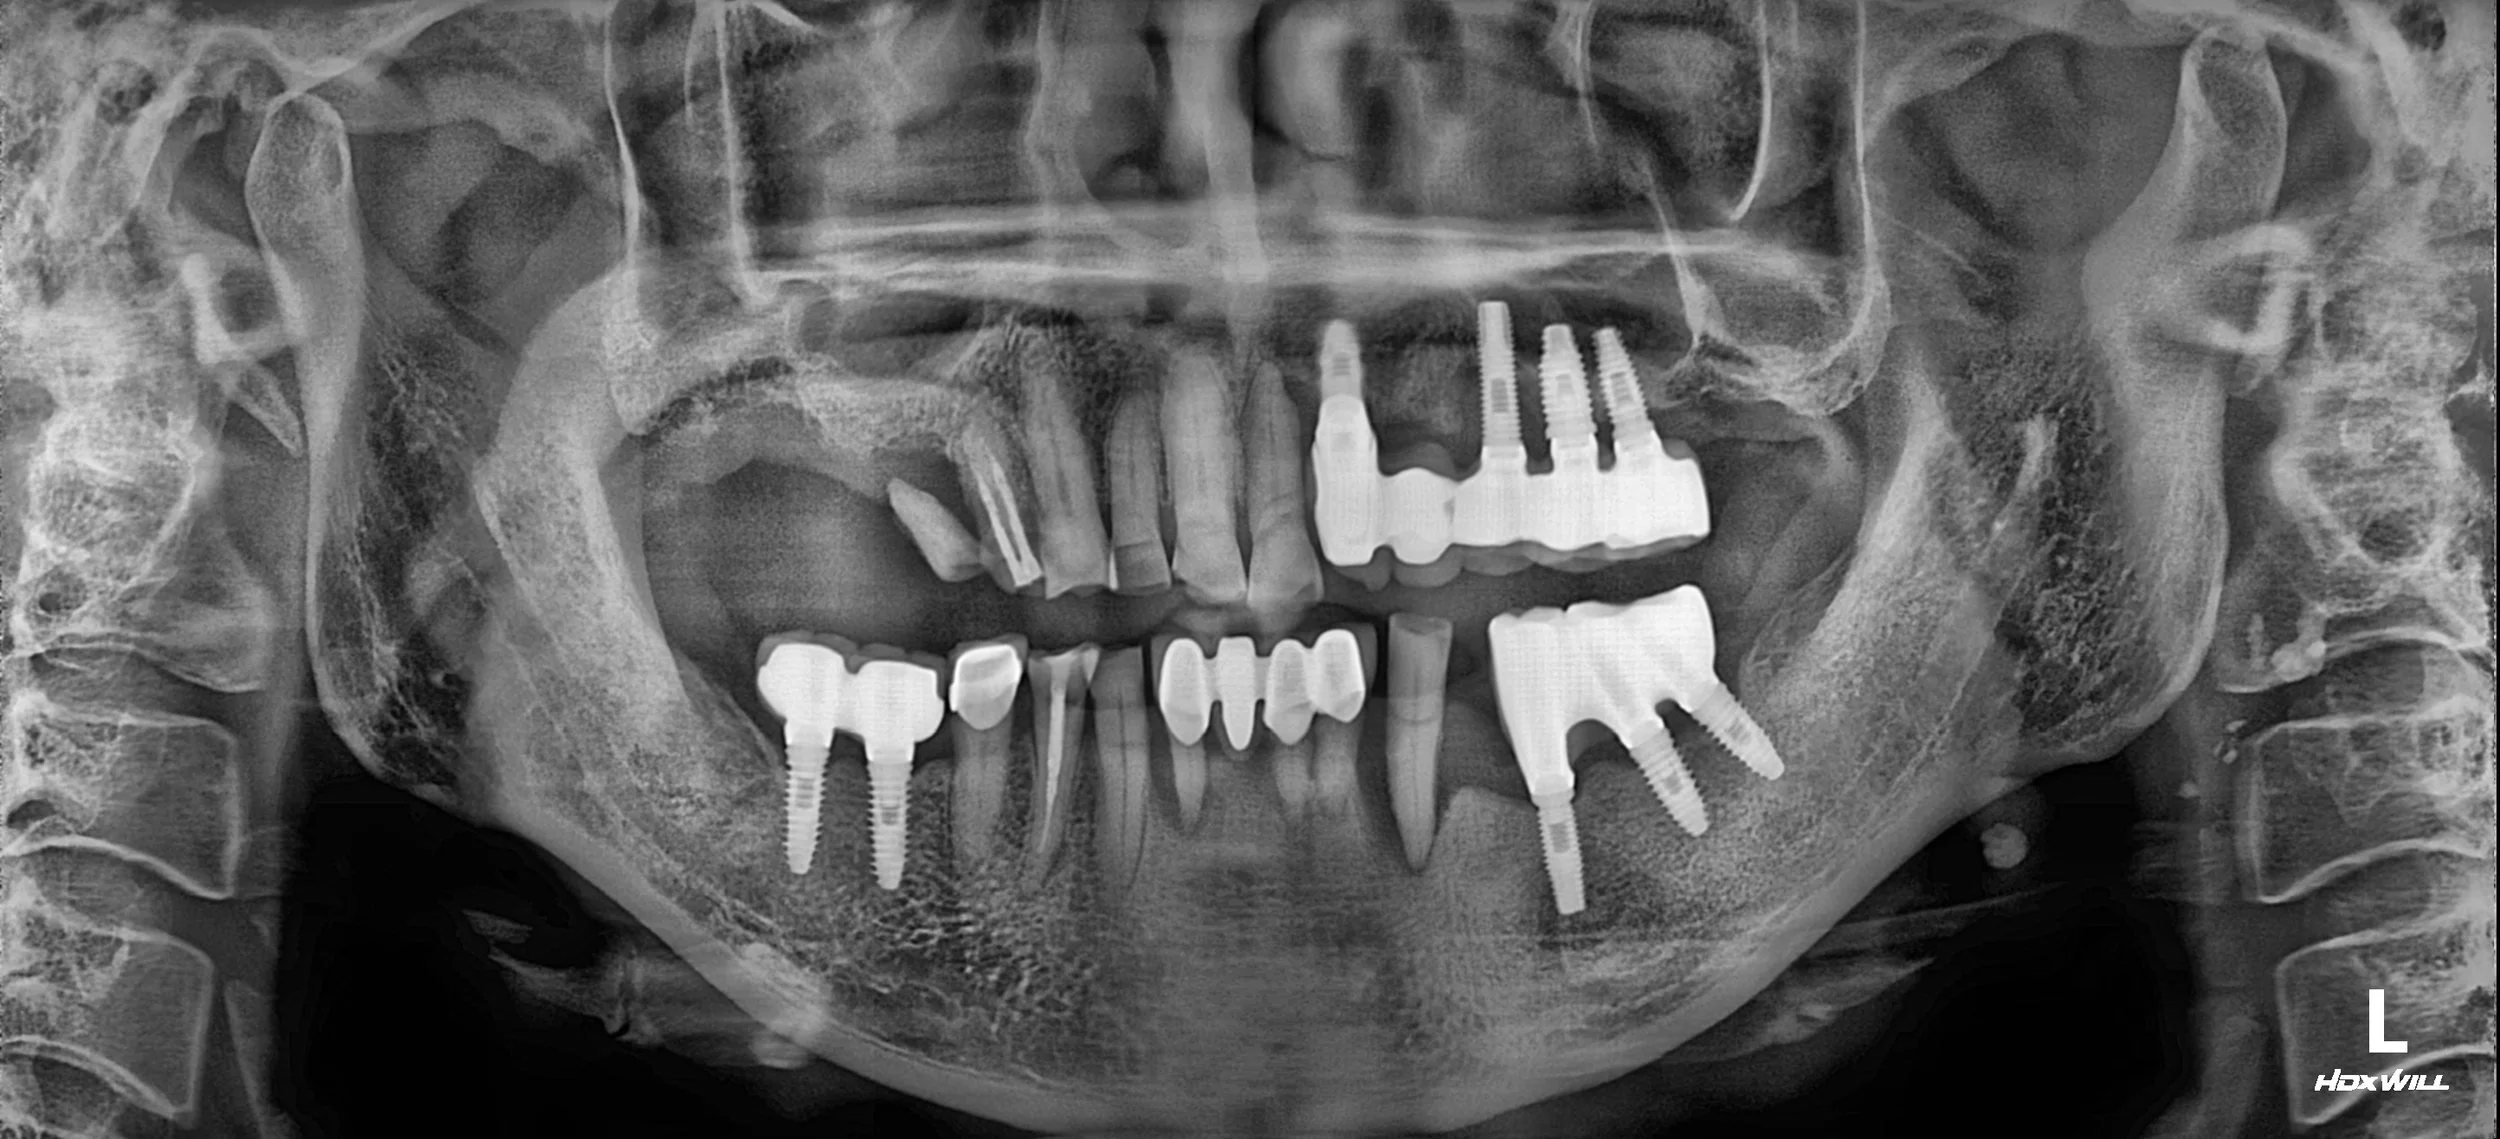

OPG - BEFORE